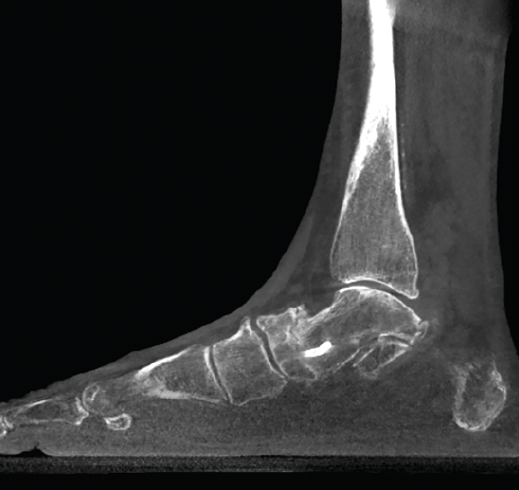

Figura 4. Estudio de la articulación subtalar bilateral.

- Patología y deformidad subtalares. Estudio de la configuración subtalar y artropatía de la misma (Figura 4).